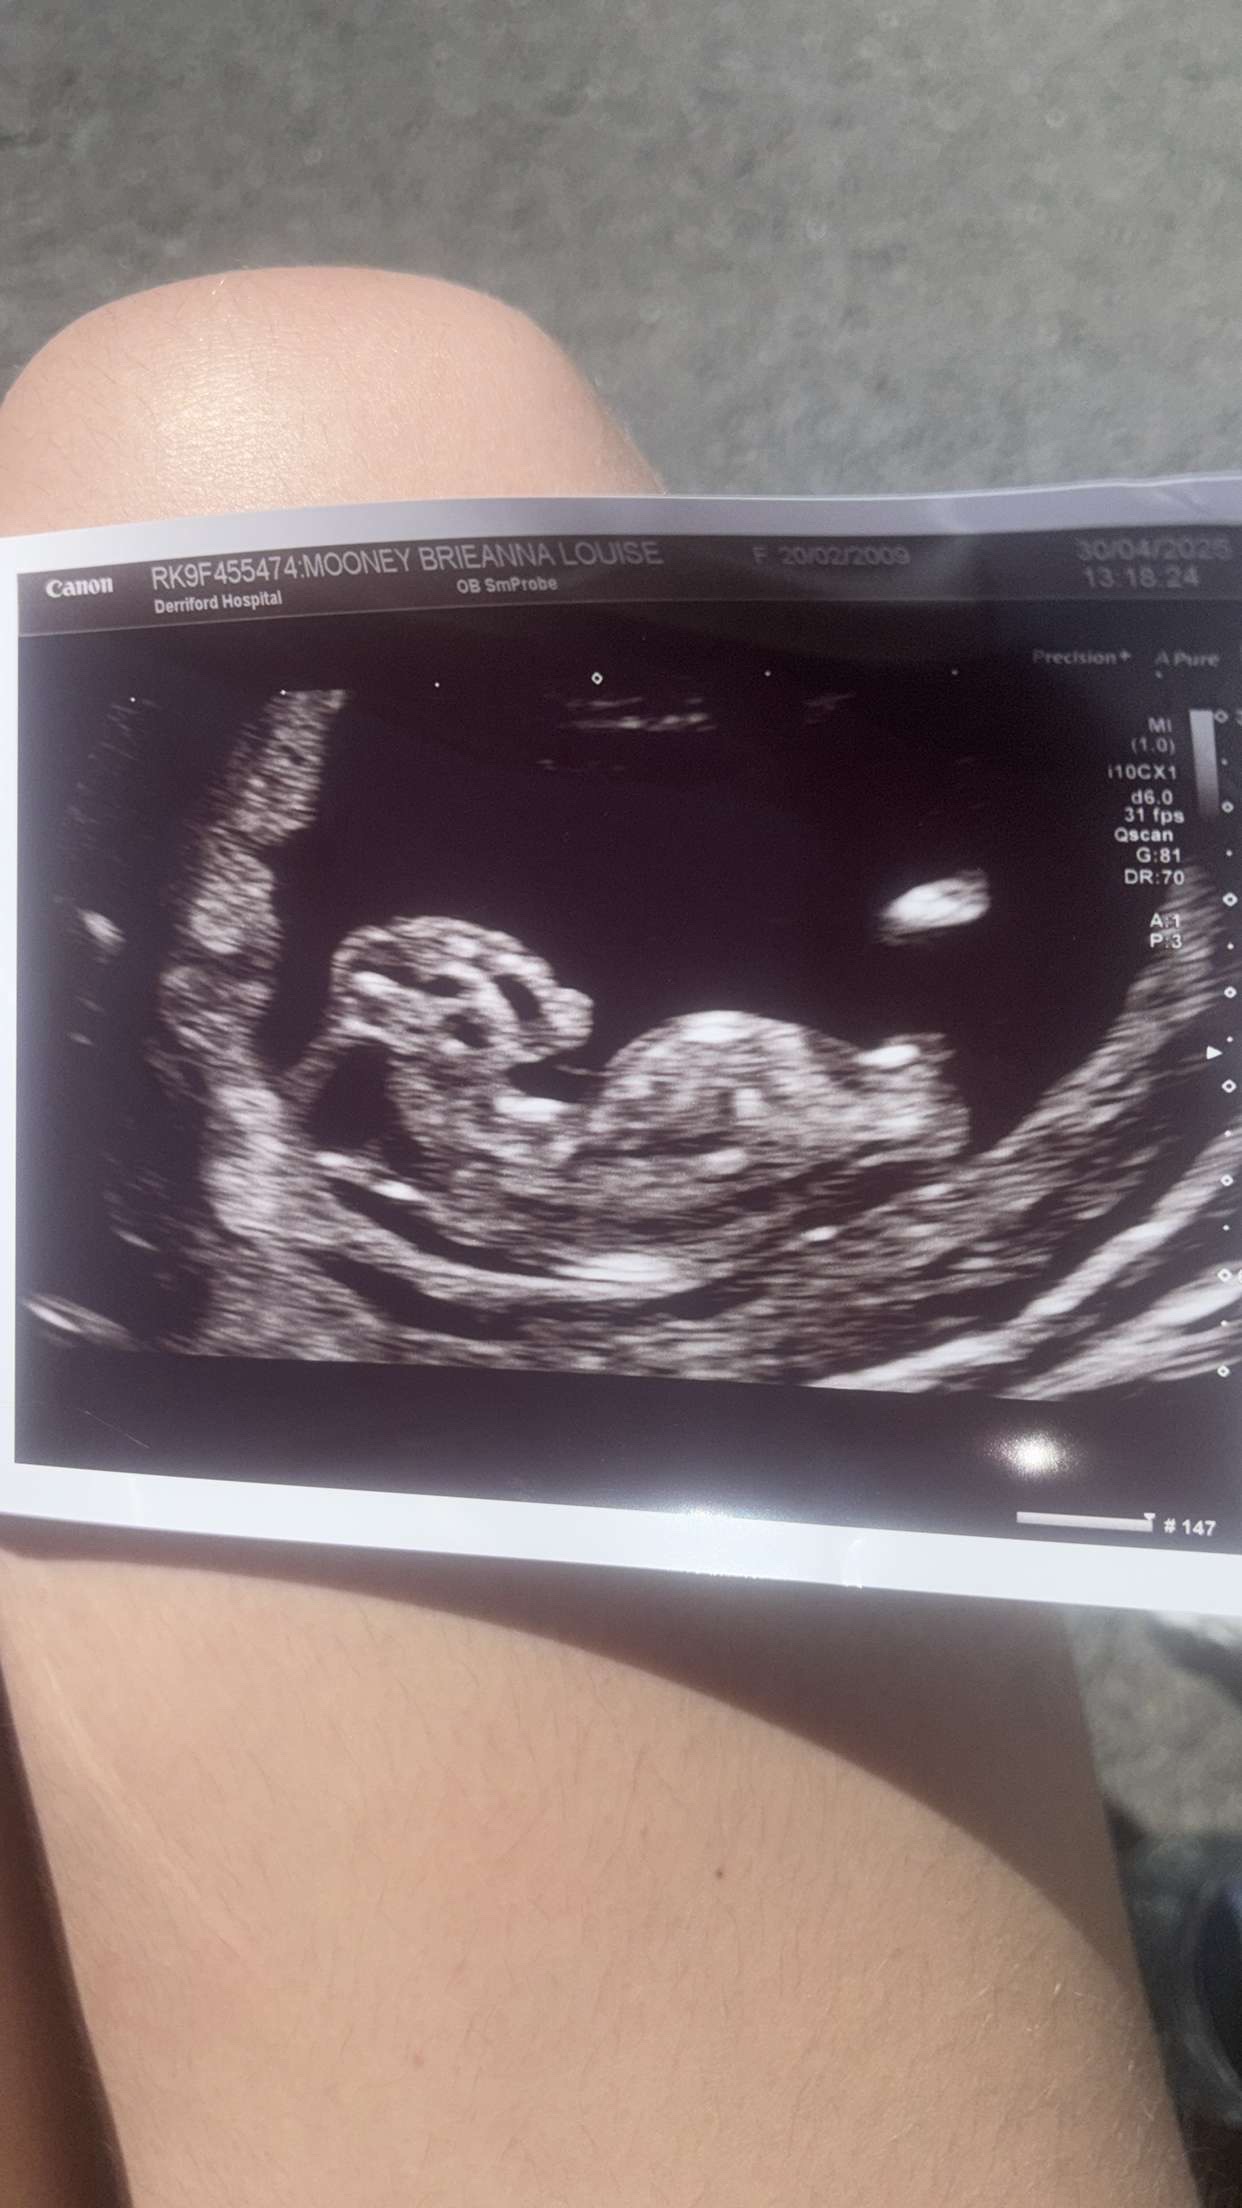

Hi my name is Logan. Unfortunately, on the 30/04/2025, my best friend, Bree, found out during her 12 week scan that her beautiful baby girl had a condition called anencephaly. This meant that tragically her baby had an underdeveloped skull and brain. Unfortunately, there is no cure for this, meaning Bree will sadly have to terminate the pregnancy, To commemorate Vienna, we ask for some donations, so that we can hold a memorial for Vienna. Any and all donations are greatly appreciated, thankyou for reading.